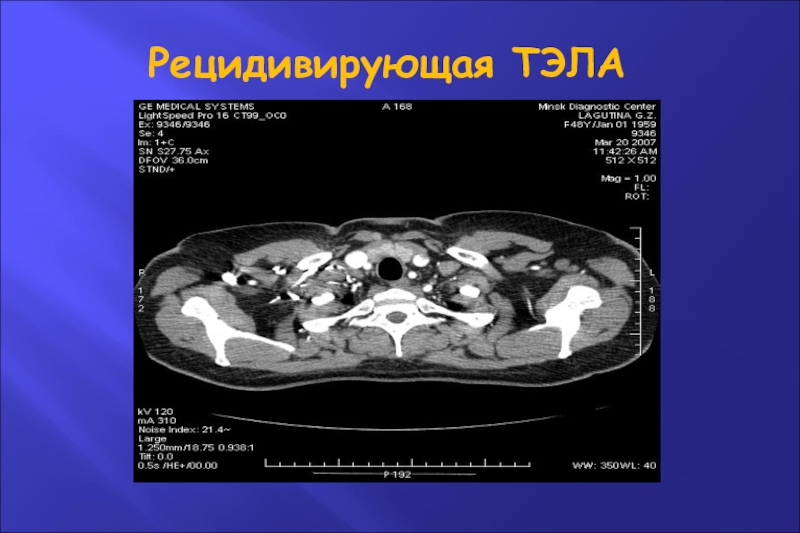

Слайд 51Рецидивирующая ТЭЛА

Рецидивирующая ТЭЛА